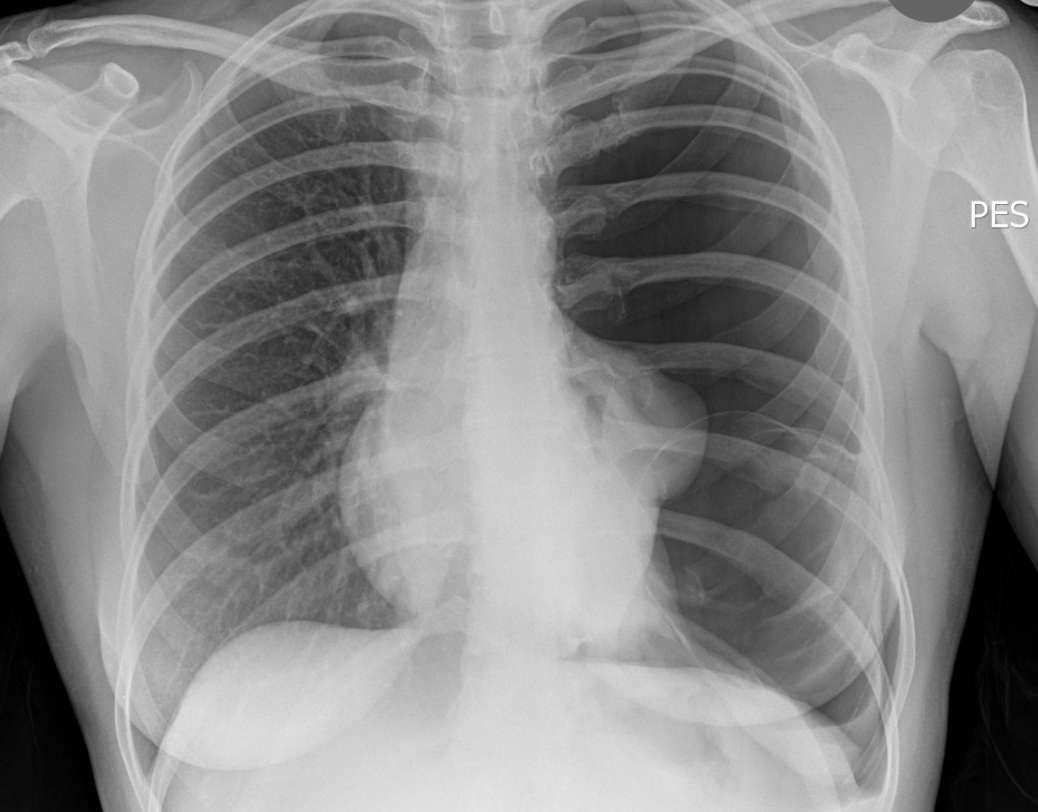

A 38-year-old woman was referred to the emergency department with a 2-week history of progressive breathlessness with no chest pain. Past medical history of asthma.

On examination she had reduced oxygen saturation (91%) on 2L oxygen, was slightly tachycardic (110 b.p.m.) and had reduced air entry in the left lung.

What’s the diagnosis ?